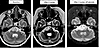

Radiographic tumor response to WP1066 treatment.Figure 3

Radiographic tumor response to WP1066 treatment. Serial brain MRIs from a pediatric patient with progressive DIPG (AflacST1901-01) who had completed a 2-week course of palliative focal re-irradiation to the tumor 12 weeks before starting study treatment show 33.8% reduction in tumor volume after 2 cycles of WP1066 treatment compared with baseline MRI obtained 2 days before the start of study treatment (15.48 cm3 to 10.25 cm3). The patient was successfully tapered off high-dose corticosteroids and improved clinically, from being wheelchair bound to walking with assistance. Subsequent brain MRI performed after 3 cycles of WP1066 while off steroids for 4 weeks (pre–cycle 4) showed a 61.8% increase in tumor volume from baseline (25.05 cm3), but no increase in intratumoral blood perfusion, suggesting that the increase in tumor volume was due to treatment-related changes. Because of the increase in tumor volume, the patient was taken off protocol therapy per the study guidelines; however, the patient continued to exhibit clinical improvement followed by stability for an additional 6 months.